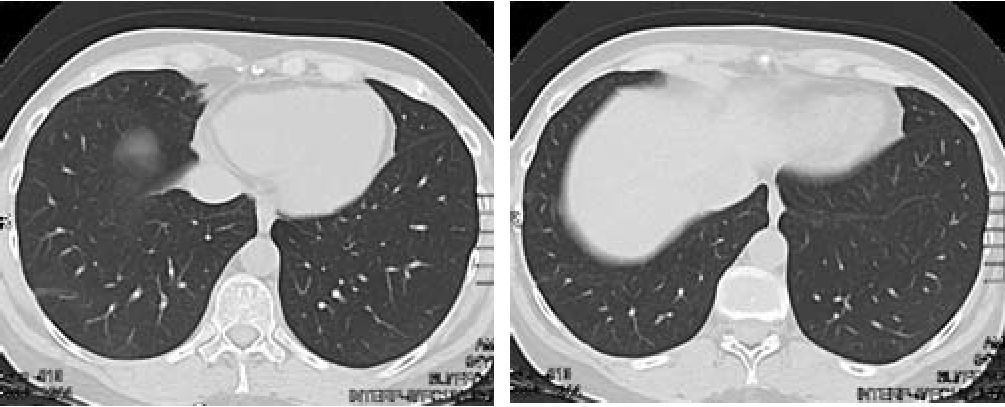

В день поступления больной была проведена КТ органов грудной клетки.

На серии томограмм, выполненных в режиме мультиспиральной КТ, в S8-S10 с обеих сторон определяется неоднородное уплотнение легочной ткани за счет инфильтративных изменений, на фоне которых прослеживаются просветы бронхов. Широким основанием инфильтрация прилежит к костальной плевре, направлена к корню легкого (рис. 1). В остальных отделах обоих легких очаговые, инфильтративные, полостные изменения не выявлены. Легочный рисунок без особенностей. Корни легких не расширены, структурны. Просветы бронхов прослеживаются до субсегментарного уровня. Просвет трахеи не деформирован, свободен. Свободной жидкости в плевральных полостях, полости перикарда не обнаружено. Органы средостения, диафрагма расположены обычно. Внутригрудные, над- и подключичные, подмышечные лимфатические узлы не увеличены. Сердце, крупные сосуды без особенностей. Костные структуры на исследованных уровнях без деструктивных изменений.

Рис 1. Рентгеновская компьютерная томография 08.07.10. Аксиальная проекция.

В заднебазальных отделах легких в проекции S8-S 10 определяется неоднородное уплотнение легочной ткани с визуализируемыми просветами бронхов, широко прилежащее к висцеральной плевре.

Спустя 2 нед. от начала лечения наблюдалась дальнейшая положительная динамика: отсутствие жалоб, уменьшение СОЭ до 42 мм/ч, при контрольной КТ грудной клетки - уменьшение размеров и плотности инфильтратов в легких (рис. 6).

Рис 6. Рентгеновская компьютерная томография 29:07.10 Аксиальная проекция.

Через 2 недели стероидной терапии выраженная положительная динамика в виде значительного уменьшения выраженности, размеров и интенсивности выявляемых ранее изменений.

Еще через 2 мес. инфильтрация в ткани легких уже не определялась (рис. 7), СОЭ - 30 мм/ч, СРБ - 4 мг/л.

Рис. 7. Рентгеновская компьютерная томография 08.10.10 Аксиальная проекция.

Через 2 месяца полный регресс ранее выявляемых изменений.